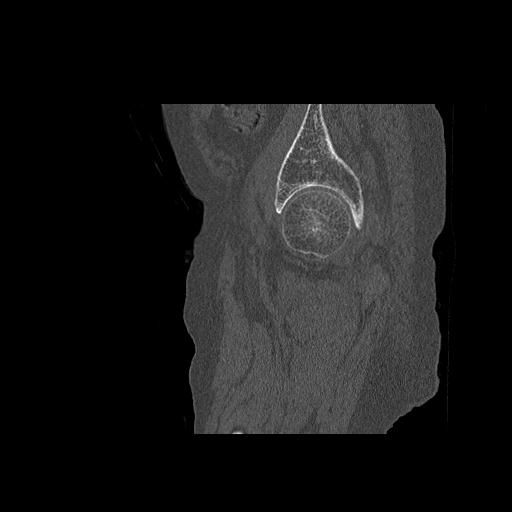

46666 1/28 両股正面+軸と 1/26 右手関節 2R 76歳女性 右転子部骨折